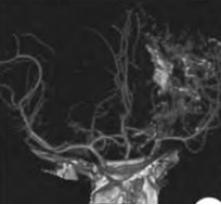

Parry-Romberg综合征

(进行性面偏侧萎缩症)

Parry-Romberg综合征是一种少见的病因不明的疾病,临床上以单侧面部皮肤及皮下组织进行性萎缩为特征,部分患者可出现肌肉和骨骼萎缩,甚至累及大脑半球。

多于10岁前发病,女性为主,起病隐匿。

神经系统受累的表现有癫痫发作、偏头痛、偏瘫、肢体萎缩、三叉神经痛等,其中癫痫发作最为常见。

颅脑MRI表现:面肌萎缩侧脑实质内钙化、大脑半球萎缩、深部及皮质下白质异常信号、软脑膜强化、颅内血管畸形、脑室扩大等。